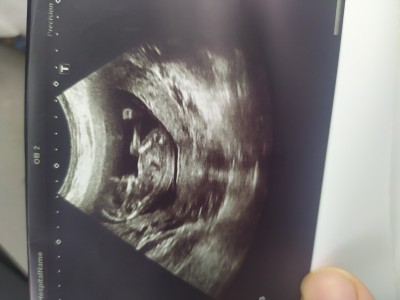

bebegim uc aydan fazla ve cinsiyeti soylemedi siz ne görüyorsunuz okadar üzgünüm ki anlatamam ya

bence erkek

Bencede erkek

Benim bebişim gibi duruşu. Bence erkek. Sen bence başka doktora daha görün derim.